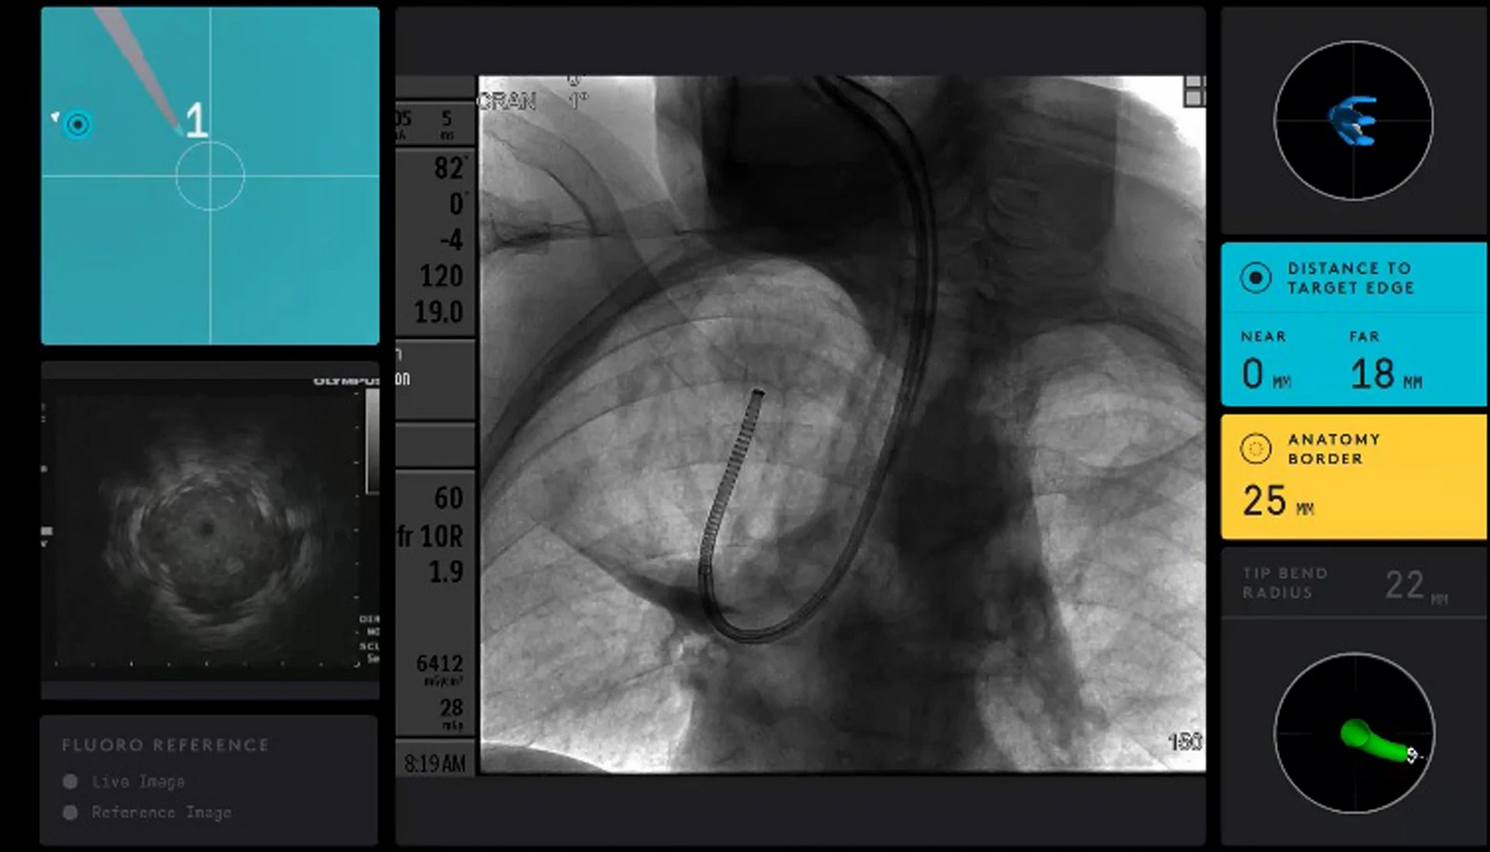

The Ion™ Endoluminal System received its FDA approval.

Robotic catheter navigated to target lesion. Biopsy needle was inserted. Initial CBCT performed. Directional adjustments made. Repeat CBCT verified location. Biopsy performed. Final CBCT used to rule out pneumothorax.